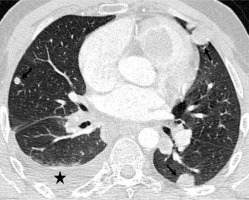

Figure 2

Axial computed tomography image show a few metastatic lung nodules (arrows) and a small right pleural effusion (asterisk)